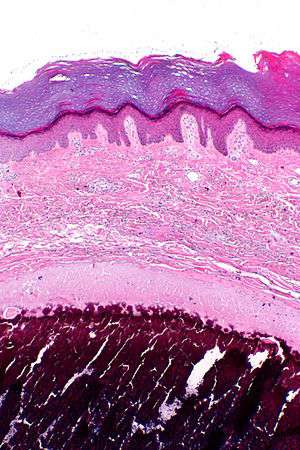

Micrograph of calcinosis cutis. The calcification is purple (bottom of image). H&E stain. | |